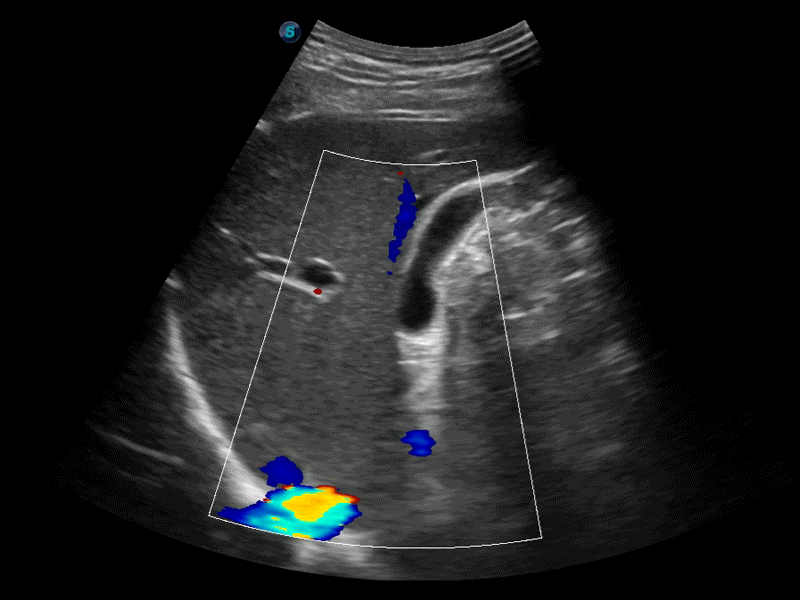

高分辨率血流成像技术提高了对低速血流信号的检测能力。在提高空间分辨率的同时,也克服了血流外溢现象,为用户提供更加真实的血流动力学信息。